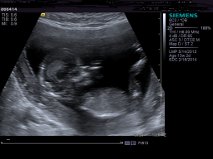

pics are really small any chance of making them bigger, i see a possible nub in the middle two pics but its hard to make out the full extent of it at that size

from the pics up i'd lean boy but not 100%